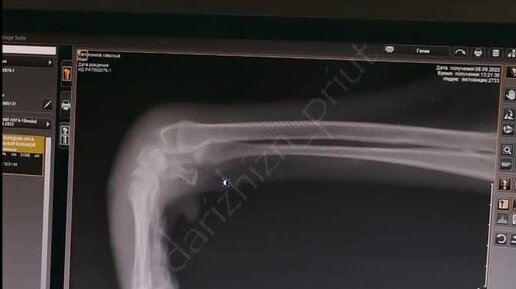

Хавроша поступил в приют с покалеченной лапкой..